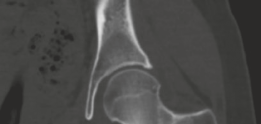

Intra-substance ossification and fracture of the ream of the acetabular roof with a cyst adjacent to the roof…